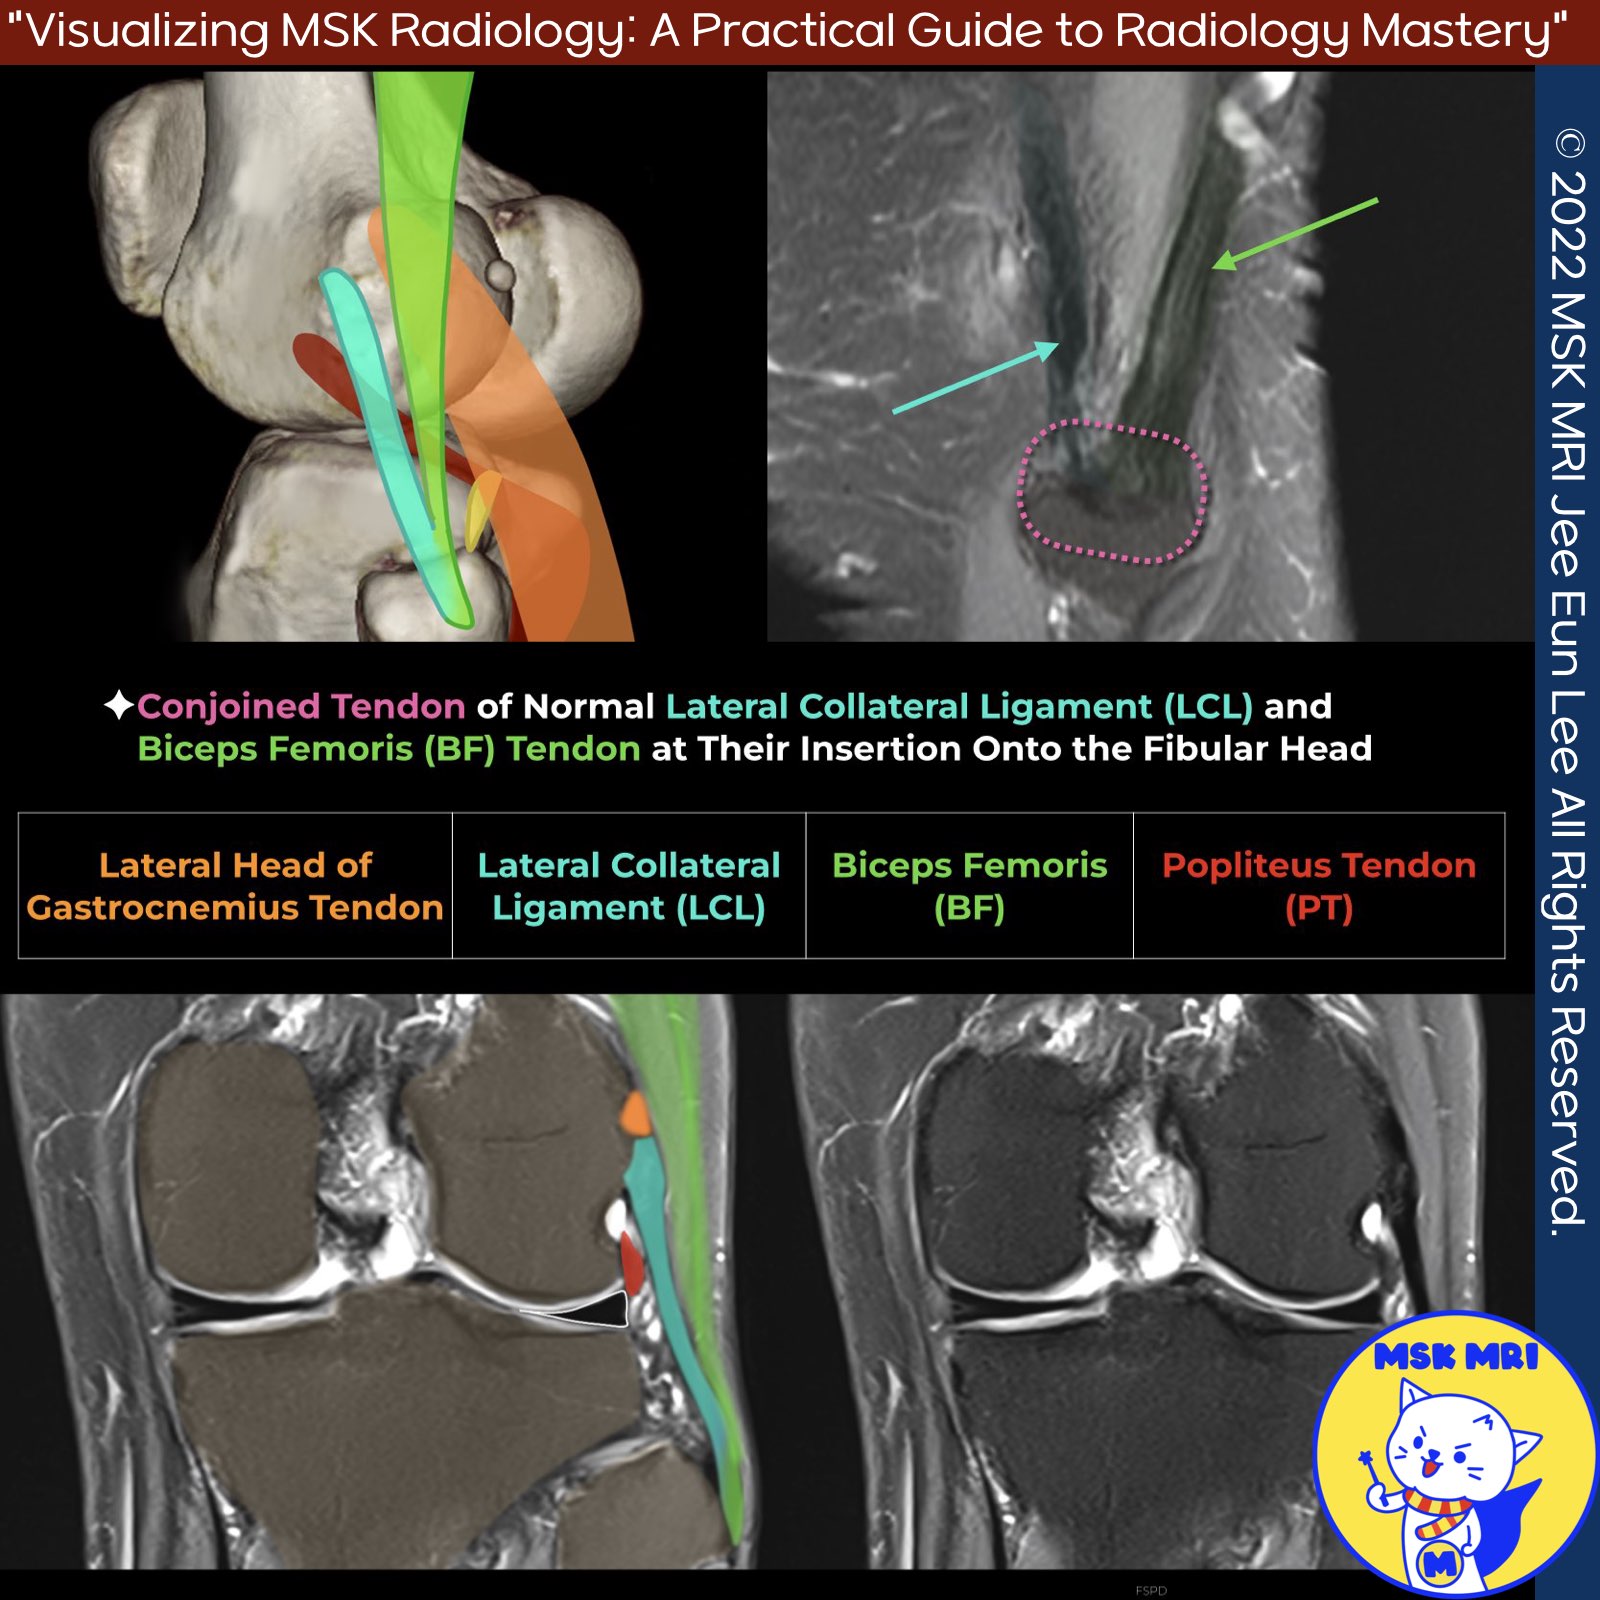

📌Anatomy of the Lateral Collateral Ligament (LCL) and Related Structures

1️⃣ Origin of the LCL

- The lateral collateral ligament (LCL) originates from the lateral side of the distal femur in a fanlike fashion, attaching between the lateral epicondyle and supracondylar process, just proximal and posterior to the lateral epicondyle, and anterior to the lateral head of the gastrocnemius muscle.

2️⃣ Insertion of the LCL

- The LCL inserts on the lateral aspect of the fibular head, anterior and lateral to the fabellofibular and arcuate ligament attachments, and distal to the fibular styloid process tip.

3️⃣ Lateral Gastrocnemius Tendon

- The lateral gastrocnemius tendon becomes adherent to the posterior knee capsule at the fabella level, inserting on the distal femur at the supracondylar process, just posterior to the LCL femoral attachment.

4️⃣ Biceps Femoris

- Tendon The LCL and biceps femoris tendon blend into a conjoined tendon distally, inserting onto the fibular head.

5️⃣ Popliteus Tendon

- The popliteus tendon attaches to the lateral femoral condyle anterior and distal to the LCL femoral origin.

- On coronal images, the popliteus insertion is seen below the lateral gastrocnemius and LCL origins.

- The lateral femoral condylar groove allows its posterior course.